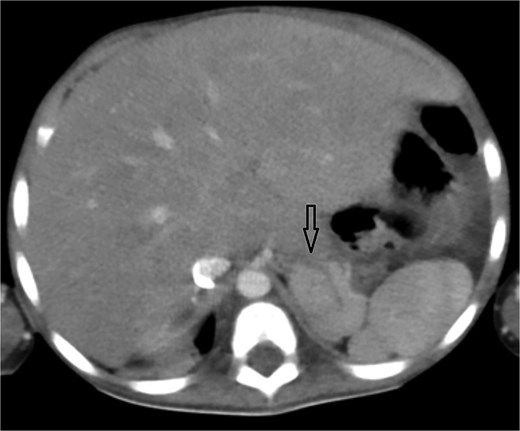

Coronal oblique maximum-intensity-projection reconstruction of thoracic CT angiography showing a large thrombosed pseudoaneurysm of the right subclavian artery at the anastomosis with the modified Blalock–Taussig–Thomas shunt, causing significant mediastinal mass effect.

Urgent transthoracic echocardiography demonstrated a large echodense mass in the right hemithorax, compression of the right atrium and reduced flow through the right-sided shunt. Computed tomography angiography (CTA) confirmed a massive saccular pseudoaneurysm (≈8 × 7 × 6 cm) arising from the anastomosis between the right subclavian artery and the mBTTS graft, completely thrombosed without active contrast extravasation (Fig. 1). There was complete thrombotic occlusion of the right pulmonary artery, right lung collapse due to extrinsic compression and right lower-lobe consolidation consistent with pneumonia (Fig. 2). CTA also revealed left isomerism with central liver and polysplenism (Fig. 3) and a horseshoe kidney (Fig. 4), suggesting a previously unrecognized polymalformative syndrome.